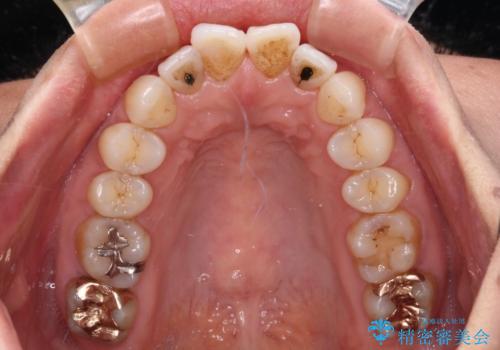

- 前方に飛び出した前歯を気にして来院された患者様です。

通常であれば上下左右の第一小臼歯4本を抜歯して口元の突出感を改善しますが、下顎前歯が1本欠損しており、上下の歯の数がアンバランスであるため、4本抜歯するかどうか悩むところでした。

上顎前歯はやや小さめで、下顎前歯はやや大きめであったため、上下左右4本を抜歯しても左右奥歯の咬み合わせは理想に近い状態を達成できると判断し、上下左右の第一小臼歯4本を抜歯し、ワイヤー装置にて矯正治療を行うこととしました。

当初目論見通り、左右奥歯の咬み合わせはしっかりとさせることができました。

下唇に跡がつくほど飛び出していた上顎前歯も引っ込み、満足のいく仕上がりとなりました。